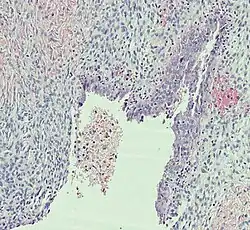

Histopathology

In case an ovarian cyst is surgically removed, a more definite diagnosis can be made by histopathology:

Type Subtype Typical microscopy findings Image

Functional cyst Follicular cyst

Corpus luteum cyst